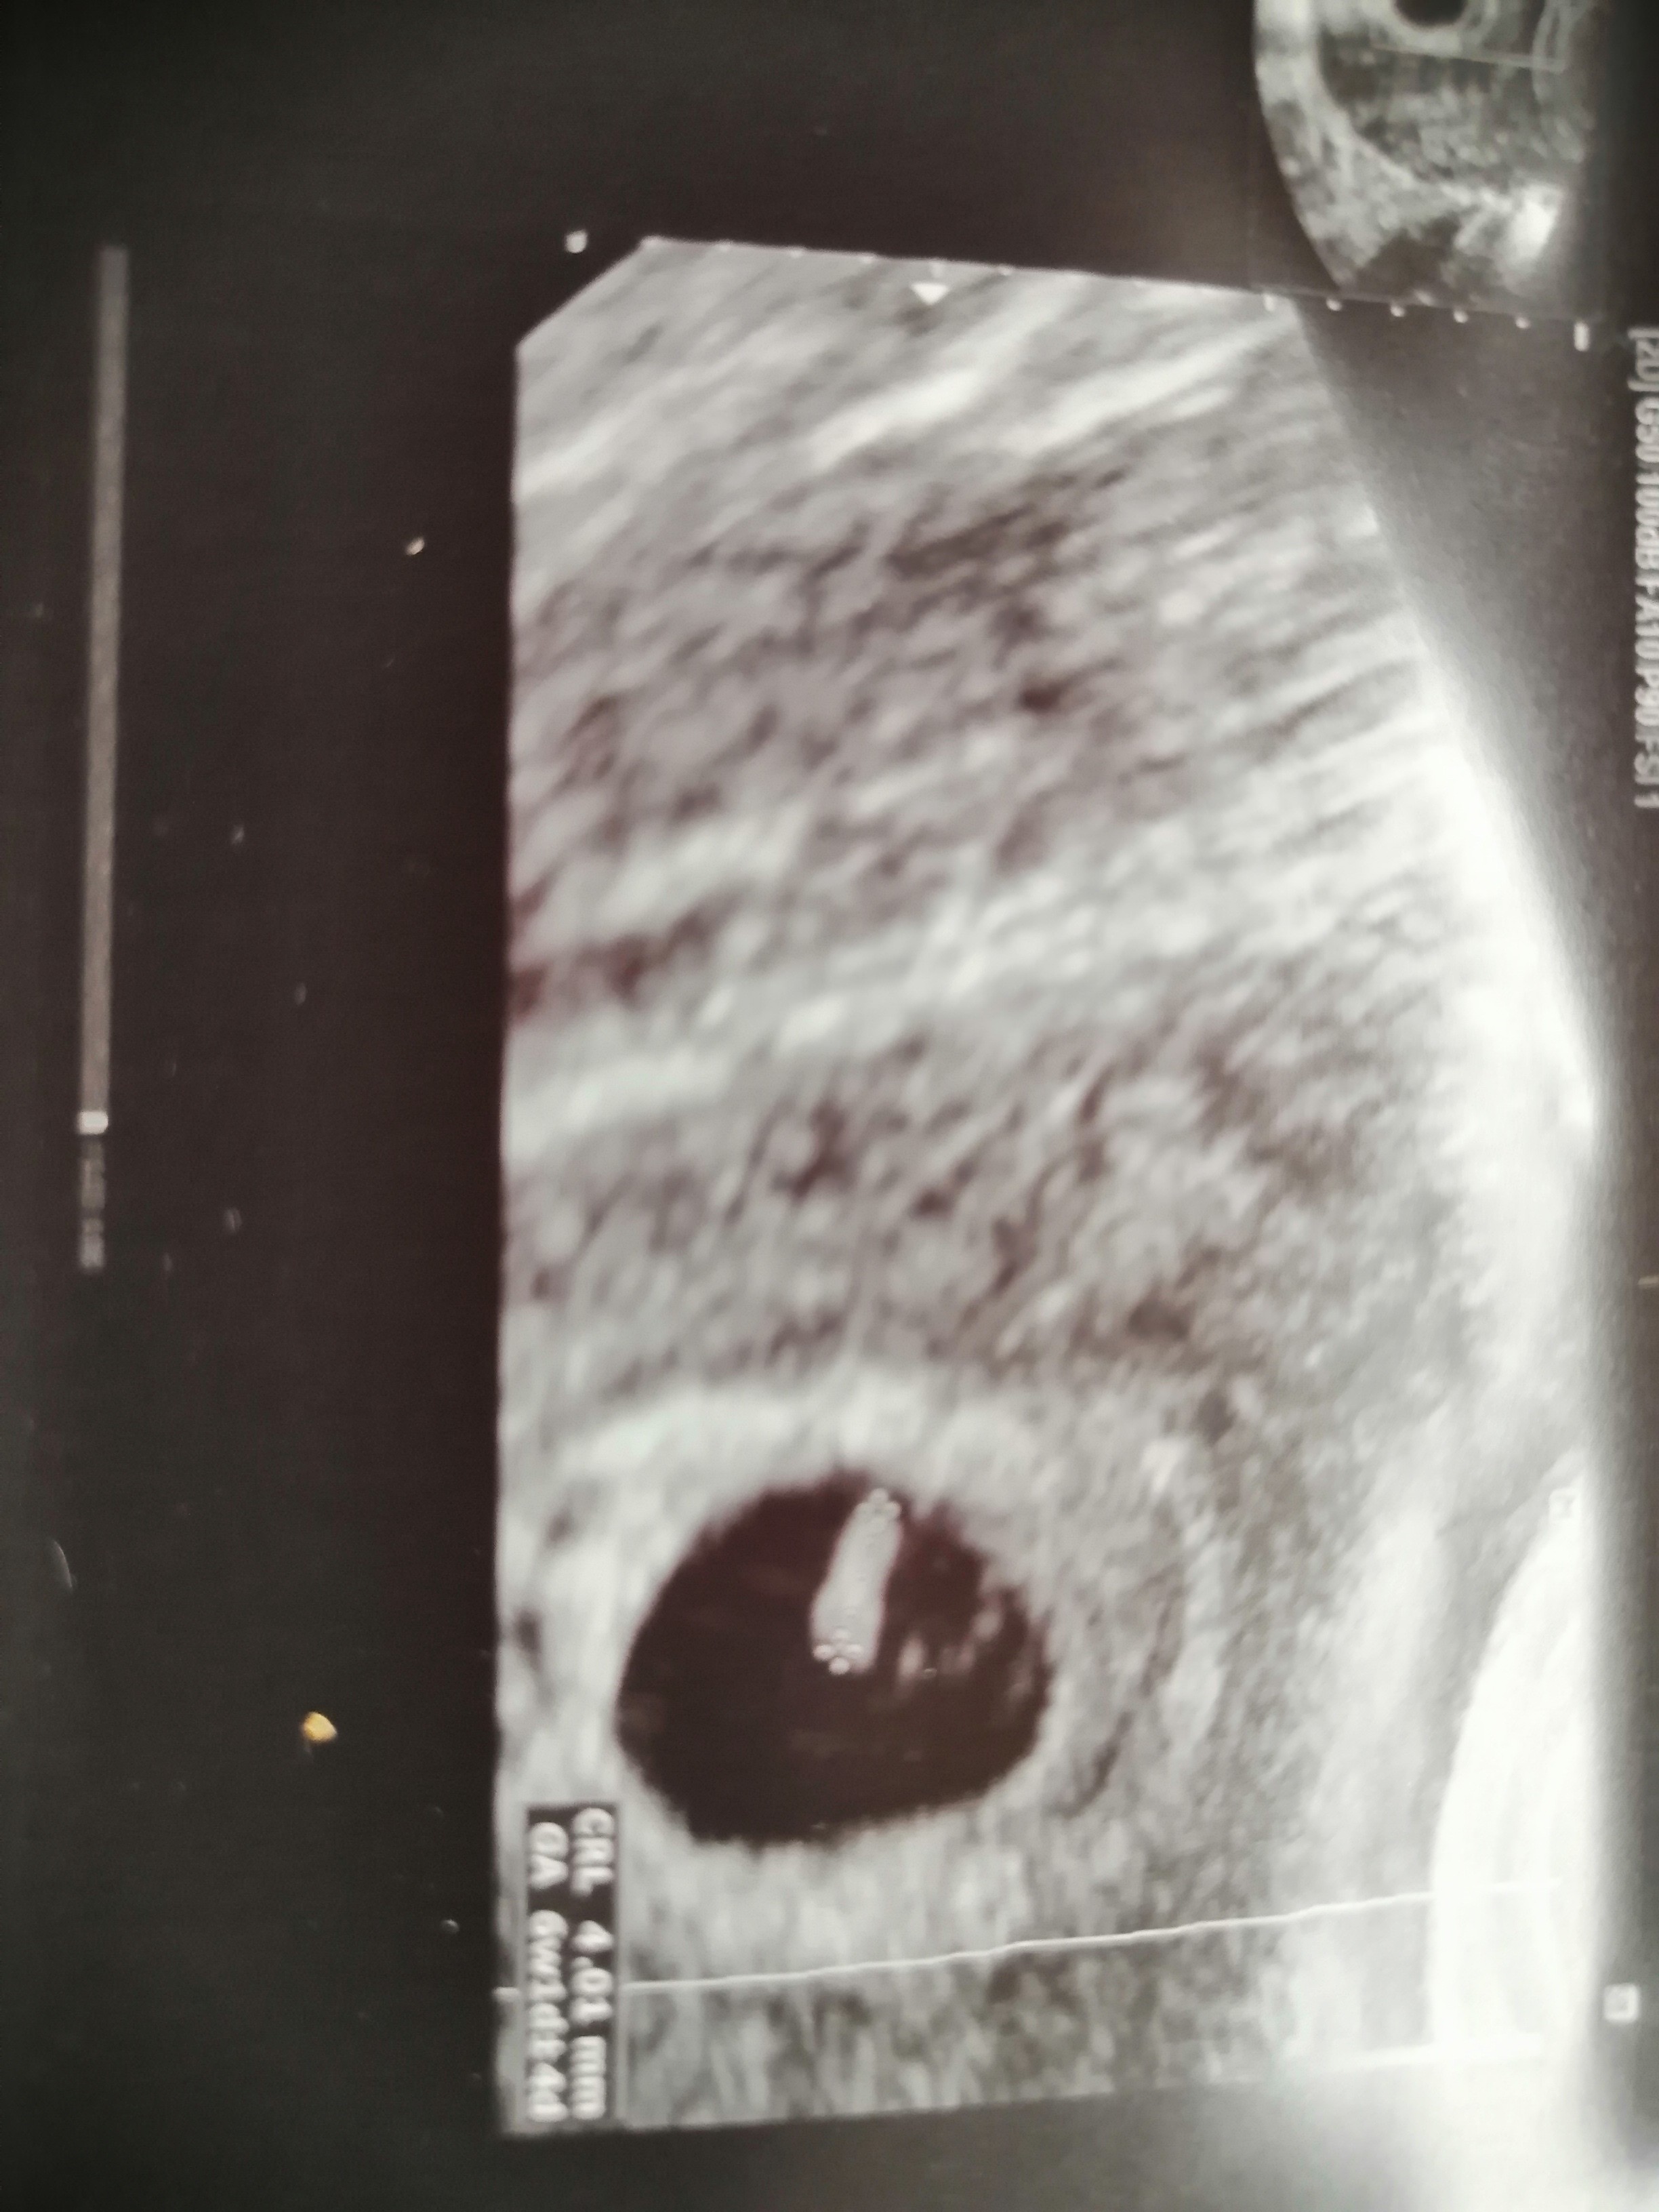

Mój pierwszy pozytywny test był 8.12, a miałam dziś 4 mmna pewno tam nic nie będzie już za tydzień...

Ale zarodek był 4 mm a nie pęcherzyk chyba